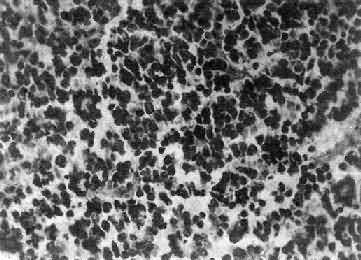

肉眼观,组织呈鱼肉状,色灰红。镜下,肿由圆形、椭圆形或胡萝卜形细胞构成,胞核着色深,胞浆少而边界不清楚,有多少不等的核分裂像。细胞密集,间质中有纤细的纤维,血管不多。细胞环绕一个嗜银性纤细的神经纤维中心作放射状排列形成典型的菊形团(图16-26),这对髓母细胞的病理诊断有一定的意义。细胞具有向神经元及神经胶质双向分化的潜能,既能向神经母细胞、节神经细胞分化,也能向胶质母细胞、星形胶质细胞分化。如细胞侵入软脑膜,可在蛛网膜下腔脑脊液中广泛播散转移。

细胞较小,着色深,密集排列,有菊形团形成